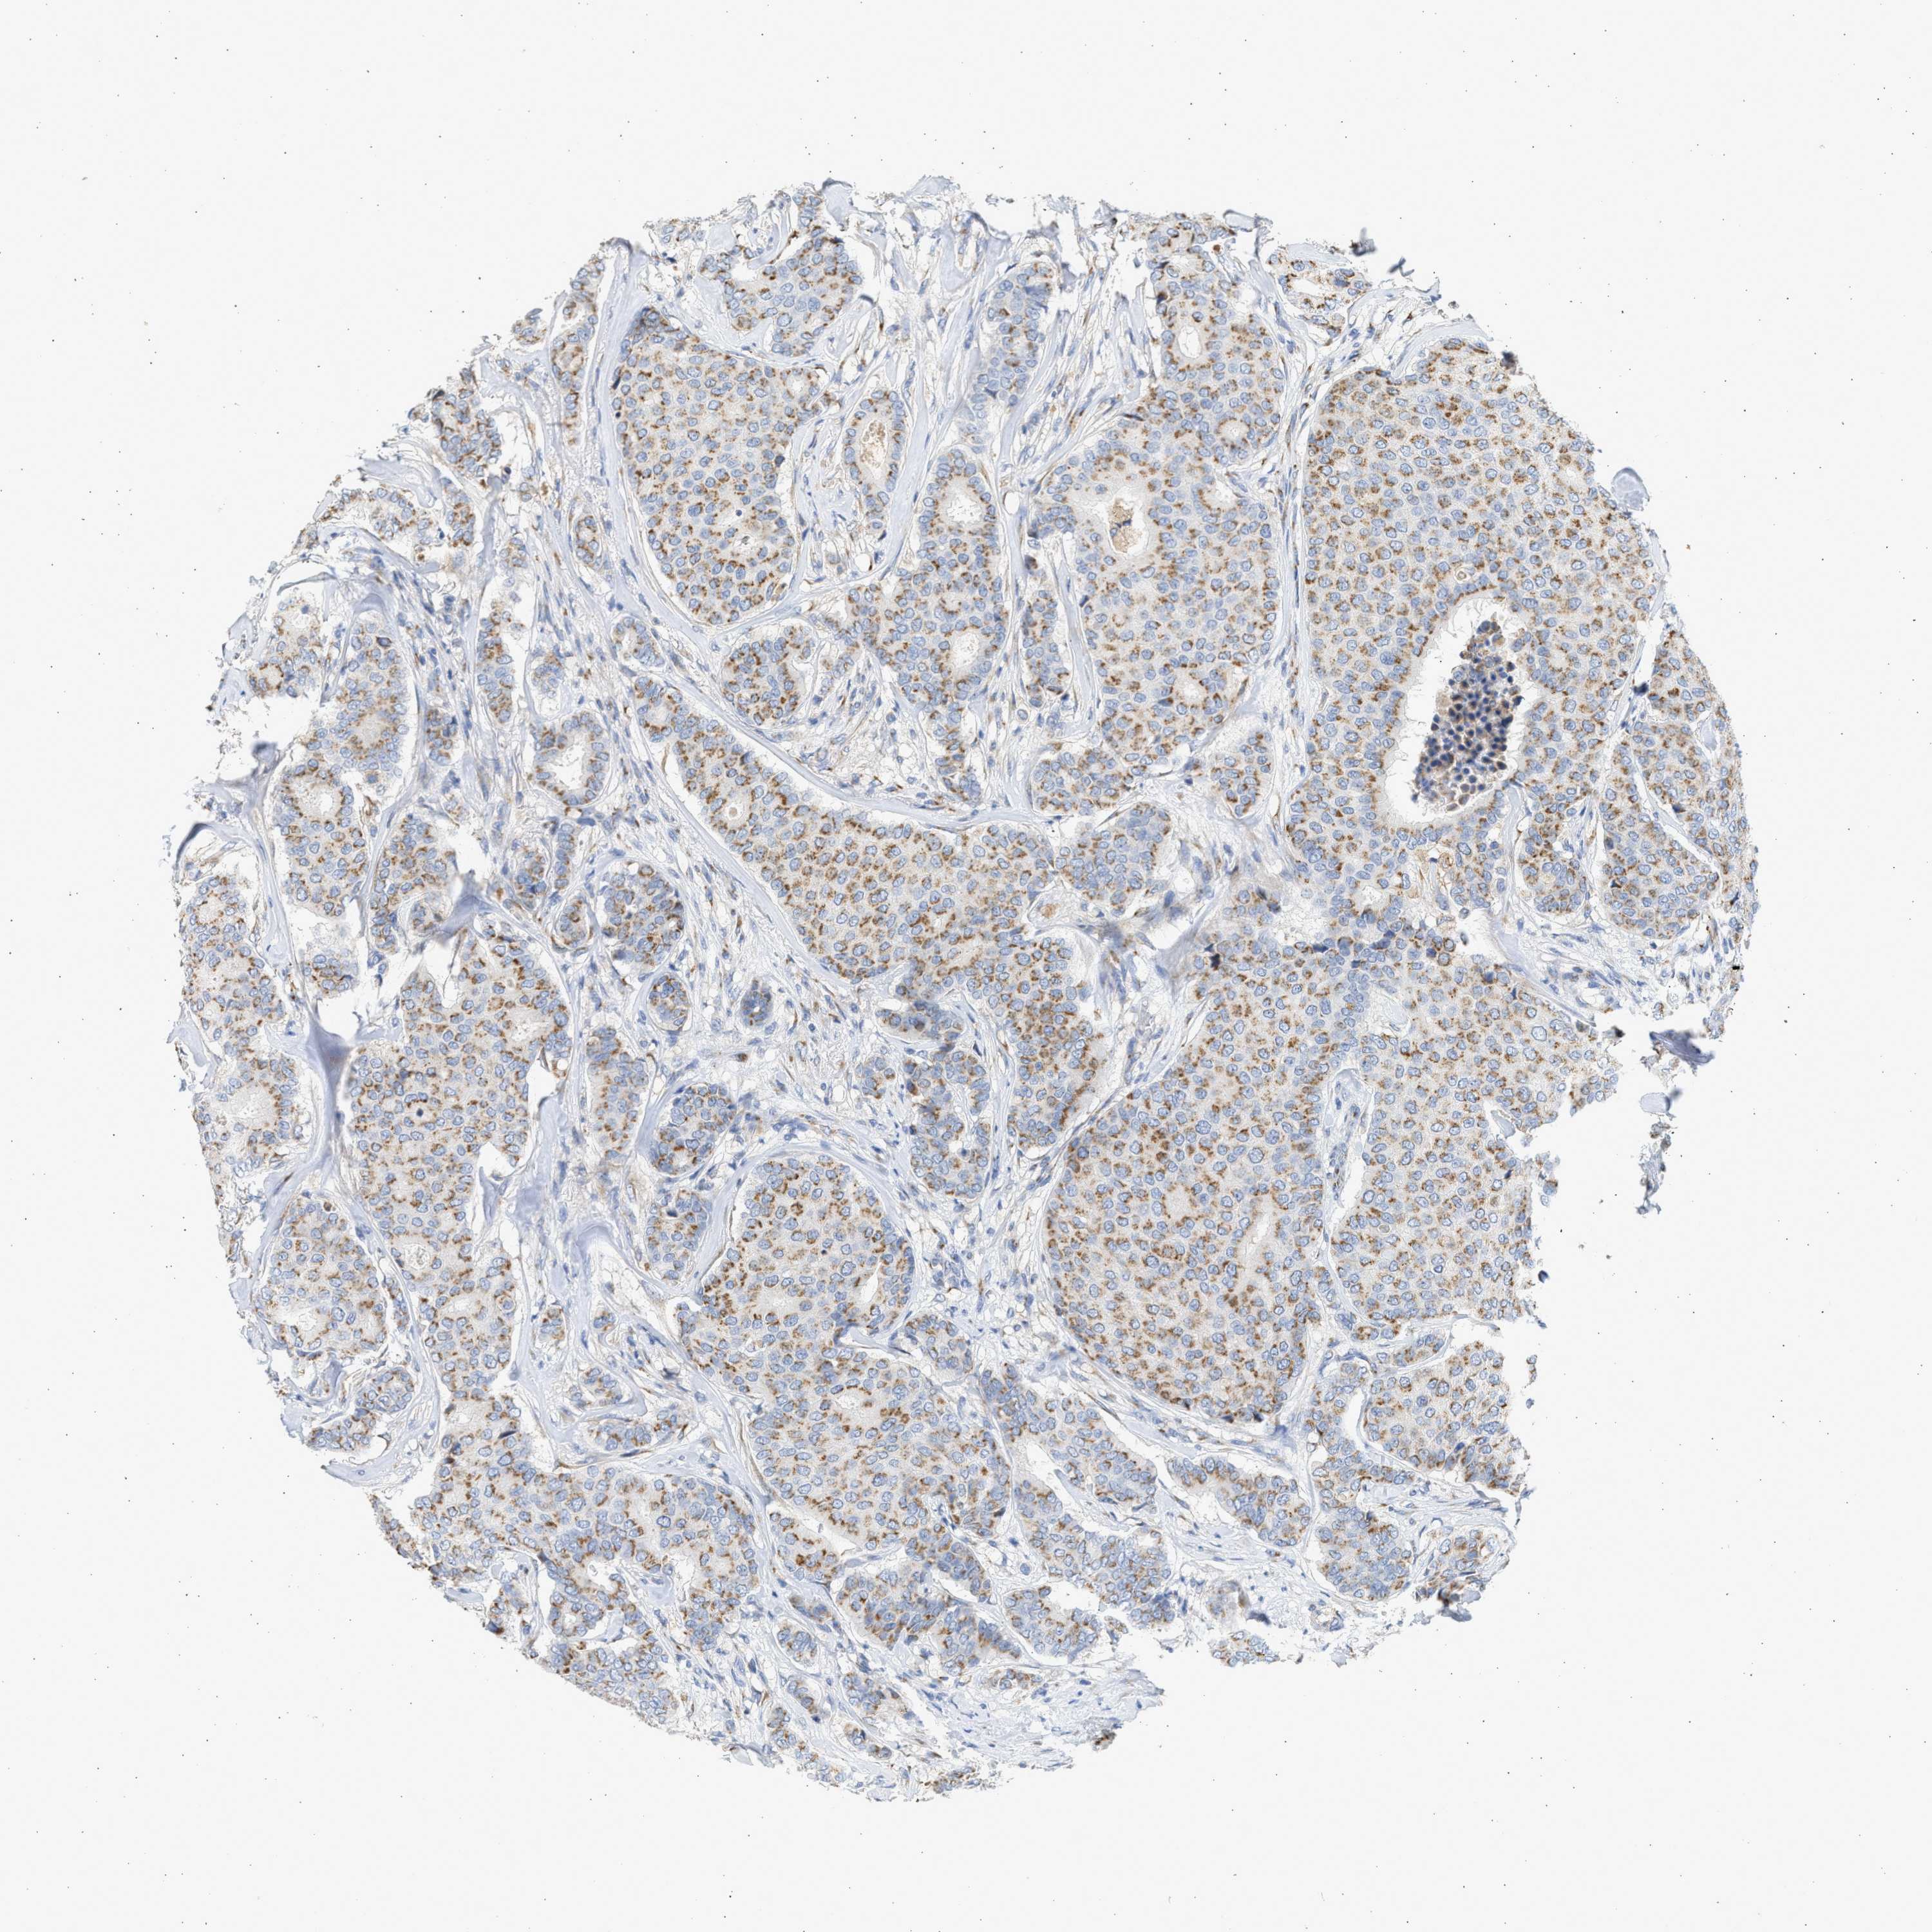

CANCER BREAST CANCER Show tissue menu

BRCA TCGA BRCA VALIDATION PROTEIN EXPRESSION